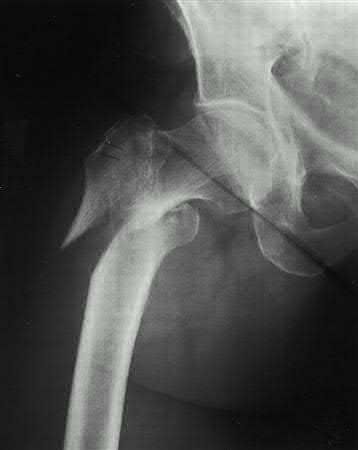

A 22-year-old woman sustains the injury seen in Figure 12 as a result of a motor vehicle crash. What factor is most closely associated with development of osteonecrosis?

Location of the fracture within the femoral neck Corrent answer: 1

A displaced femoral neck fracture in a young patient is considered a surgical urgency and prompt anatomic reduction and internal fixation is recommended. There are a few studies that have specifically looked at the rate of osteonecrosis in this patient population. A review of femoral neck fractures in patients ages 15 to 50 years revealed that the incidence of osteonecrosis in displaced fractures was 27% compared with 14% in nondisplaced fractures.

The quality of the reduction also influenced the rate of osteonecrosis. Time to reduction, type of implant, presence or absence of capsulotomy, and location of the fracture are not associated with osteonecrosis risk.